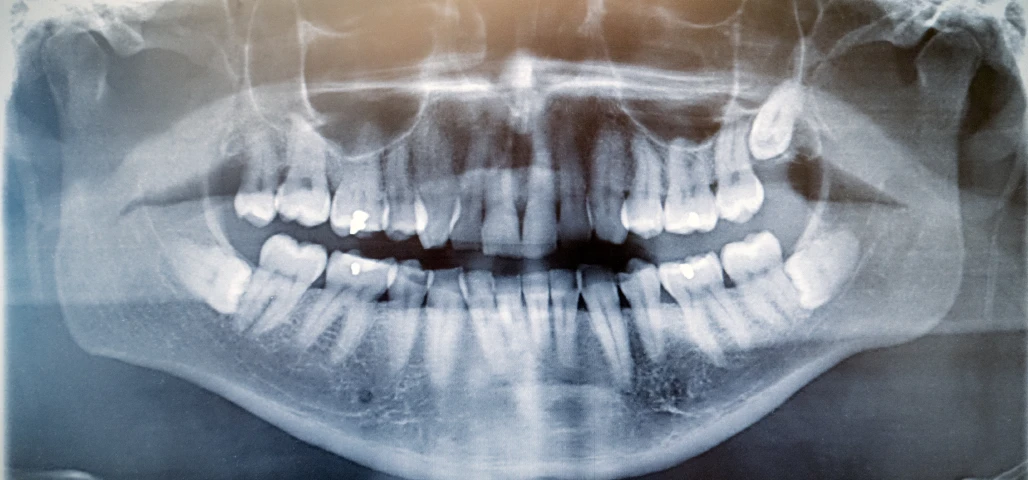

La chirurgie orale regroupe un ensemble d’interventions réalisées au niveau de la bouche, des dents et des mâchoires, allant de l’extraction des dents de sagesse aux actes plus complexes comme les kystes, les freinectomies ou les préparations implantaires.